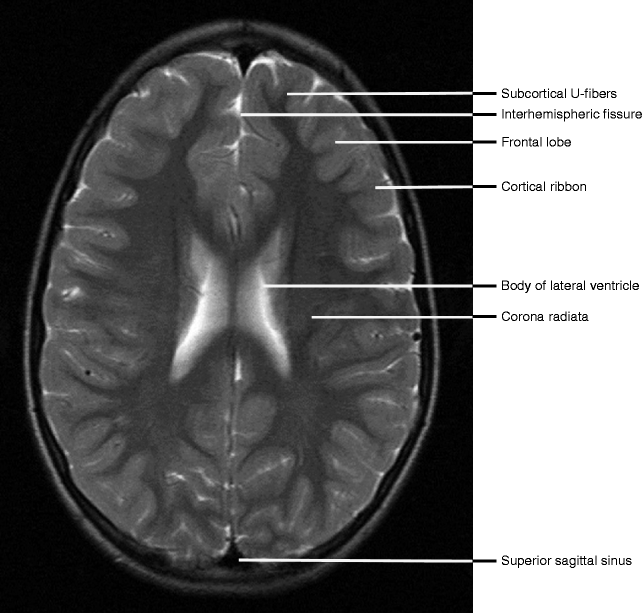

Normal Anatomy Radiology Key

radiologykey.com